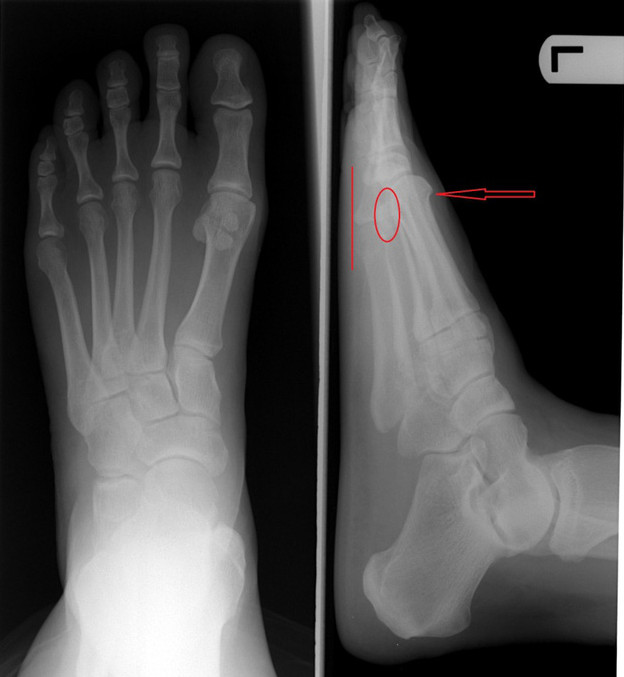

Picture 2 of The unexpected truth about the forefinger was longer than the big toe In the X-around photo, when the index finger is longer, the big toe bone is also pressed and bent close to it.